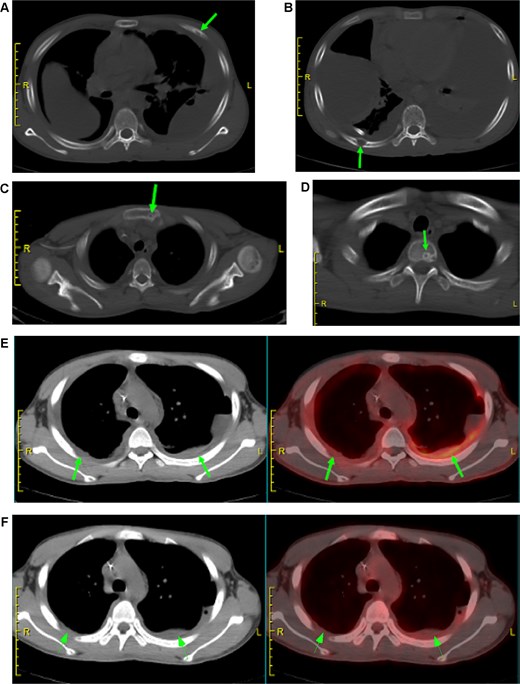

December 2023, he was admitted to our hospital for further diagnosis and treatment. The chyle test for pleural effusion was positive. Staphylococcus aureus was found in pleural effusion culture. Serum carbohydrate antigen 125 was the only elevated tumor marker (212 U/mL; reference value: 0–24 U/mL) despite a full panel being tested in both serum and pleural fluid. No malignant cells were detected in the effusion. Other laboratory parameters fell within normal ranges or demonstrated only minor deviations. A positron emission tomography-computed tomography (PET/CT) scan demonstrated generalized decreased bone density with multiple osteolytic lesions of varying sizes (Fig. 1A–D, Fig. S1). Bilateral pleural thickening was observed, showing increased fibroblast activation protein inhibitor (FAPI) metabolism without corresponding fluorodeoxyglucose (FDG) uptake (Fig. 1E and F). Electromyography revealed mild conduction slowing at the posterior borders of bilateral sternocleidomastoid muscles (left 0.3 Mv; right 0.4 Mv; reference value ≥0.7 Mv; Fig. S2). The pathological examination of the patient's right iliac bone tissue revealed progressive osteolysis (Fig. 2A), featuring sparse and slender bone trabeculae (Fig. 2B) with partial fragmentation (Fig. 2C). Together with the clinical presentation, the patient was diagnosed with GSS [6]. The patient was treated with sirolimus 2 mg once daily [7], and continued to follow a low-fat diet. Follow-up 18F-FAP-NUR PET/CT [8] scans at one year showed results consistent with the previous findings.

PET/CT findings of multifocal skeletal involvement and pleural abnormalities. (A–D, arrows) PET/CT scan demonstrates massive osteolytic destruction of the left 4th rib, right 8th rib, sternum, and a thoracic vertebra. (E, F, arrows) Bilateral pleural thickening with markedly increased FAPI uptake but absent FDG metabolism. Notes: (A–D) Arrows indicate sites of extensive osteolytic destruction with corresponding metabolic foci. (E) Arrow highlights FAPI-avid diffuse pleural thickening, suggestive of progressive fibrotic change. (F) Corresponding FDG-PET image shows no significant metabolic activity, emphasizing the differential diagnostic value of FAPI in this context.